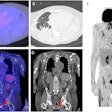

PET/CT reveals new infections in ICU patients